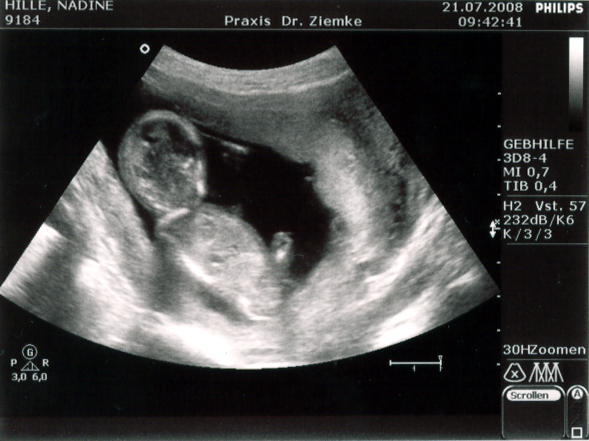

Vorhin waren wir bei Nadins neuer Frauenärztin in der Tuchmacherstraße – Annika Stellmacher heißt die. Und die schreibt nun die Fortsetzung von Nadins Mutterpass. Auf der ersten Seiten des zweiten Teils steht:

21.7. | SSW (LR) 14/4 | SSW korrigiert 13/4

SSL 6,9 | BPD 2,3

Und übersetzt heißt das, dass Nadin nicht in der 15. Schwangerschaftswoche ist, sondern erst in der 14.. Somit verschiebt sich der voraussichtliche Gerburtstermin eine Woche nach hinten – und zwar auf den 22. Januar 2009.

SSL steht für Scheitel-Steiß-Länge, und die beträgt jetzt 6,9 cm.

BPD steht für Biparietaler Durchmesser, und der ist entsprechend 2,3 cm.

Zusammenfassend bedeutet das: Alles in bester Ordnung. Das Herz schlägt, die Anzahl der Finger ist korrekt. Und Mehrlinge werden es auch nicht…